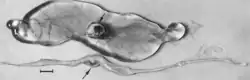

Macroscopic changes of embryos are death followed by resorption of fluids (Fig. 4) and then soft tissues (Fig. 5). Virus and viral antigen are widely distributed in tissues of infected embryos and their placentas,[84] and it is probable that microscopic lesions of necrosis and vascular damage, subsequently described for fetuses, also develop in advanced embryos.

Figure 4. Embryos from a gilt experimentally infected oronasally immediately after breeding and killed 22 days later. Bar = 1 cm. (Top) Noninfected, clinically normal embryo (arrow) and associated extraembryonic membranes; (bottom) PPV-infected, dead littermate embryo (arrow) and associated extraembryonic membranes, recent death, no obvious resorption of soft tissues.[84]